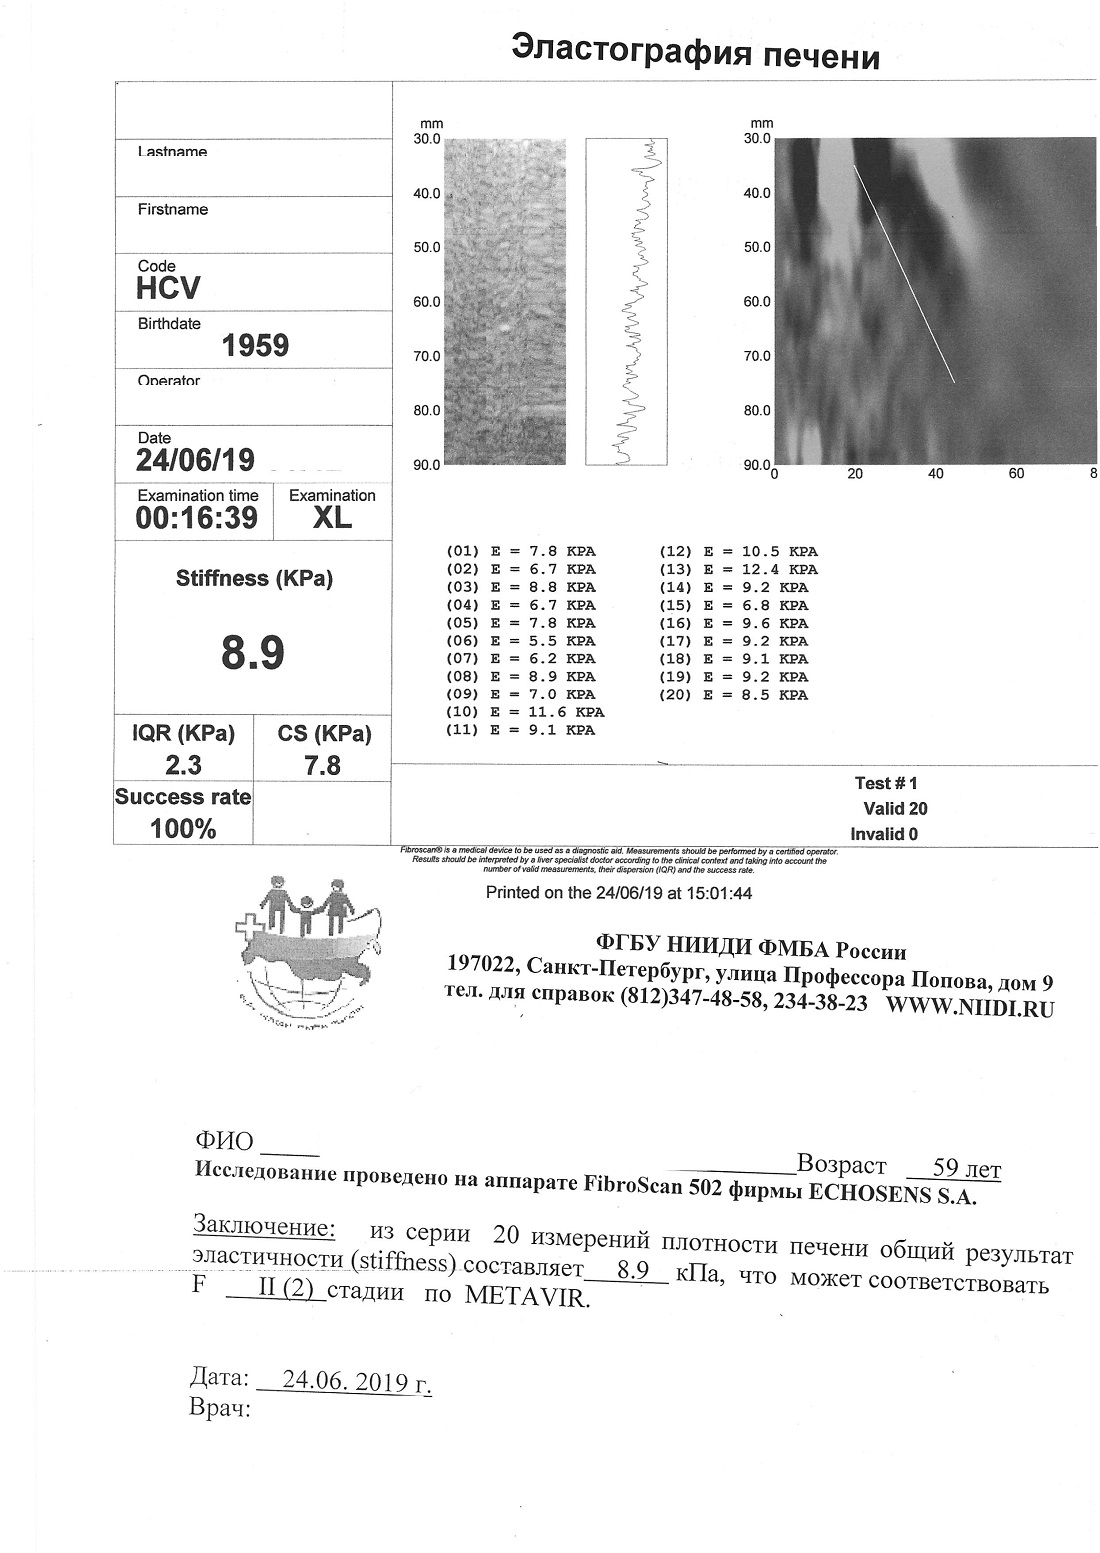

Сдали необходимые анализы: пцр-положительный; anti-HCV: положительный, все (core, ns3, ns4, ns5); генотип-1b; фиброз-2 стадии (8,9кПа); АЛТ и АСТ - небольшие превышения, количественный тест - врач, сказала не нужен.